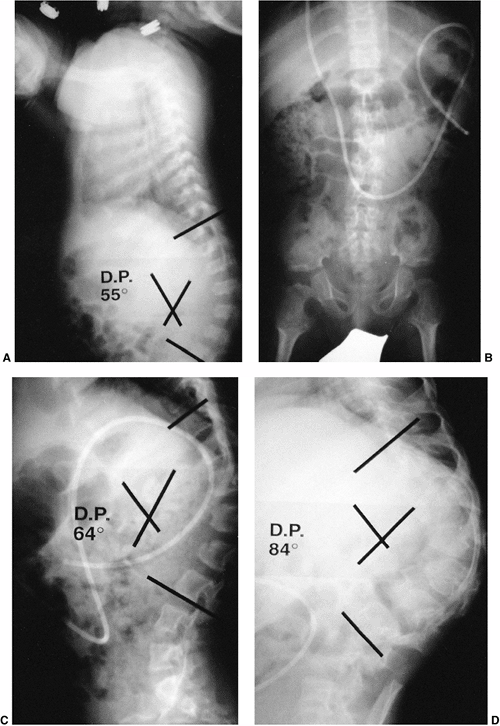

Figure 20.9 Congenital kyphosis. A and B: Anteroposterior and lateral radiographs. Note inadequate detail of kyphosis on lateral radiograph of spine. C to E:

Computerized tomography (CT) three-dimensional reconstruction views that clearly demonstrate the bony anatomy of congenital kyphosis. |